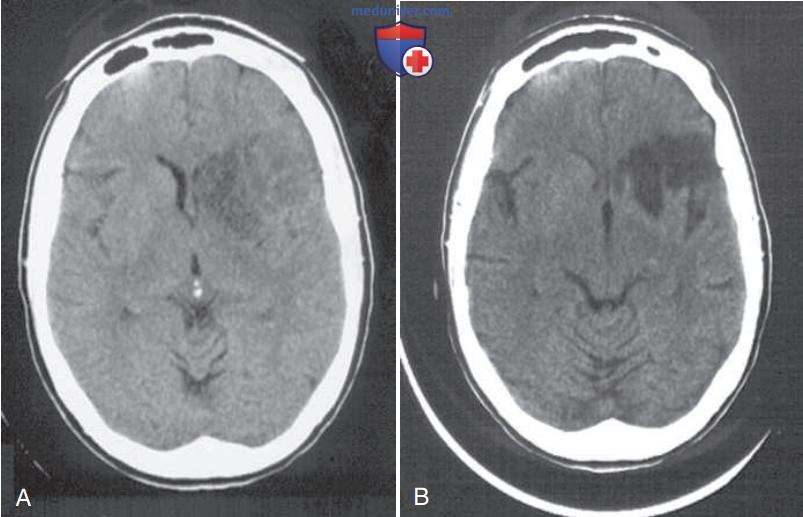

Есть очаги в головном мозге

Есть очаги в головном мозге 114 фото